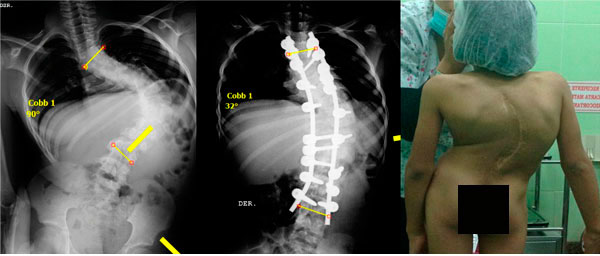

Cifosis rígida toracolumbar (Enfermedad de Scheuermann): varón de 20 años, consulta por dolor toraco lumbar intenso, realizo 4 anos de terapia física y rehabilitación sin éxito. 10 meses Post-operado, se tuvo que realizar varias osteotomías de columna, actualmente sin dolor, realiza actividades cotidianas sin limitaciones.